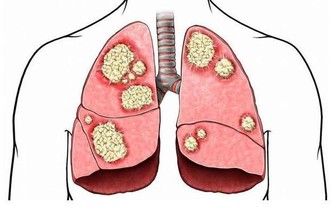

排除其他疾病。很多如腫瘤、結核、甲狀腺功能亢進症等疾病都會導致體重下降,而我提到的三種疾病都容易與糖尿病伴發而行,所以如果明顯的體重下降,首先要篩查這三種疾病,如果有隱匿的疾病沒有發現,那麼任何阻止體重減少的治療都是治標而不治本的。